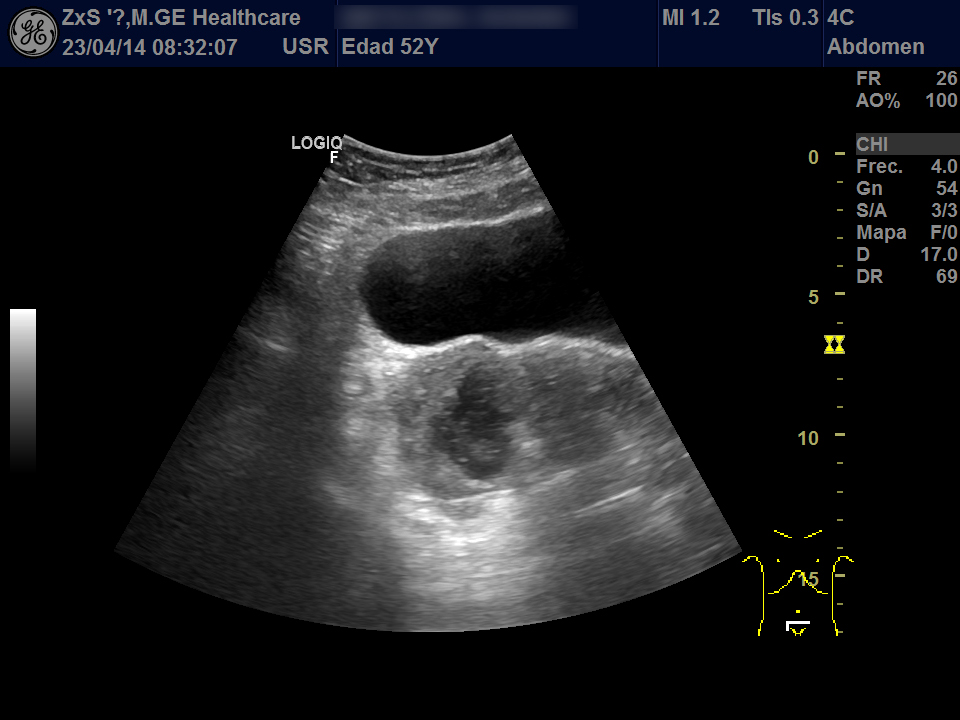

Hígado de bordes lisos y ángulo agudo, aspecto heterogéneo, no se observan LOES. Vía biliar extra e intrahepática no dilatada. Vesícula poco replecionada sin imágenes en su interior, Murphy ecográfico negativo. Ambos riñones de localización y tamaño normal. Buena diferenciación córtico-sinusal y en riñón derecho discreto aumento del tamaño de la pelvis renal compatible con hidronefrosis grado 2. Vejiga bien replecionada sin ecos en su interior. Se objetiva útero de tamaño normal con una imagen hiperecogénica que corresponde a DIU y en la zona derecha una lesión redondeada de aproximadamente 5,5 x 6,5 de diámetro de contenido heterogéneo que dudamos si puede corresponder a masa ovárica desconocida. Se deriva al hospital por sospecha de masa ovárica.

Evolución y seguimiento: Urgencias hospital TAC abdominal: en región anexial lesión de aspecto sólido-quístico de 6,5 x 5,5 cm con cambios inflamatorios de la grasa adyacente y que produce leve desplazamiento del útero hacia la izda. No se observan colecciones, neumoperitoneo, ni líquido libre intraabdominal.

Dco hospital: Absceso tubo-ovárico Ingreso. Se retira DIU y se pauta tto antibiótico IV. Posterior laparoscopia abierta: Plastrón inflamatorio que alberga trompa y anejo derecha íntimamente adherido a asas intestinales, útero y pared pélvica.